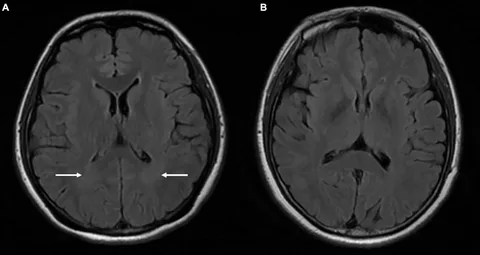

Idiopathic Intracranial Hypertension (IIH / Pseudotumor Cerebri)

IIH is a condition of elevated pressure inside the skull without an identifiable structural cause. Patients experience severe headaches, pulsatile tinnitus, visual disturbances, and risk of permanent vision loss. IIH is increasingly understood to involve venous sinus stenosis as a contributing factor, and venous sinus stenting has emerged as an effective treatment option for selected patients.

Dr. Choudhri has published research on the role of stenting in venous sinus stenosis for IIH and is a contributor to the MPRESS trial, a PCORI-funded national study evaluating treatments for IIH. His team has also published on the emerging role of GLP-1 receptor agonists (such as semaglutide) in IIH management—an exciting new therapeutic avenue.